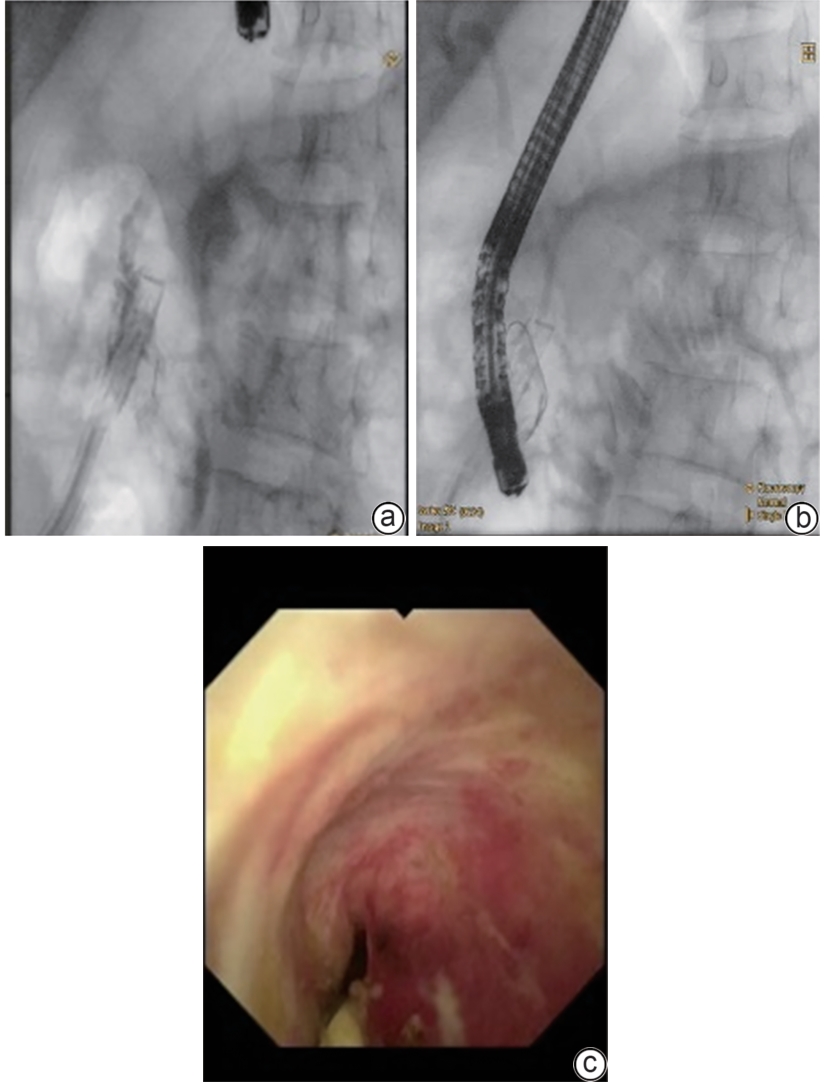

Successful treatment of biliary fistula after Beger surgery by oral choledochoscopy-assisted percutaneous-endoscopic rendezvous technique: A case report

Yuxin WANG, Weigang GU, Zheng JIN, Xiaofeng ZHANG

2025, 41(2): 333-336. DOI: 10.12449/JCH250220

Abstract(861) HTML (246) PDF (4794KB)(49)

Abstract:

Duodenum-preserving pancreatic head resection, also known as Beger surgery, has a high incidence rate of bile duct injury after surgery, while the treatment modality for bile duct injury depends on the severity of the injury, and endoscopic therapy is often challenging in case of severe bile duct injury. Recently a patient with biliary fistula after Beger surgery was admitted to Affiliated Hangzhou First People’s Hospital, Westlake University, and successful diagnosis and treatment were achieved through oral choledochoscopy-assisted percutaneous-endoscopic rendezvous technique.